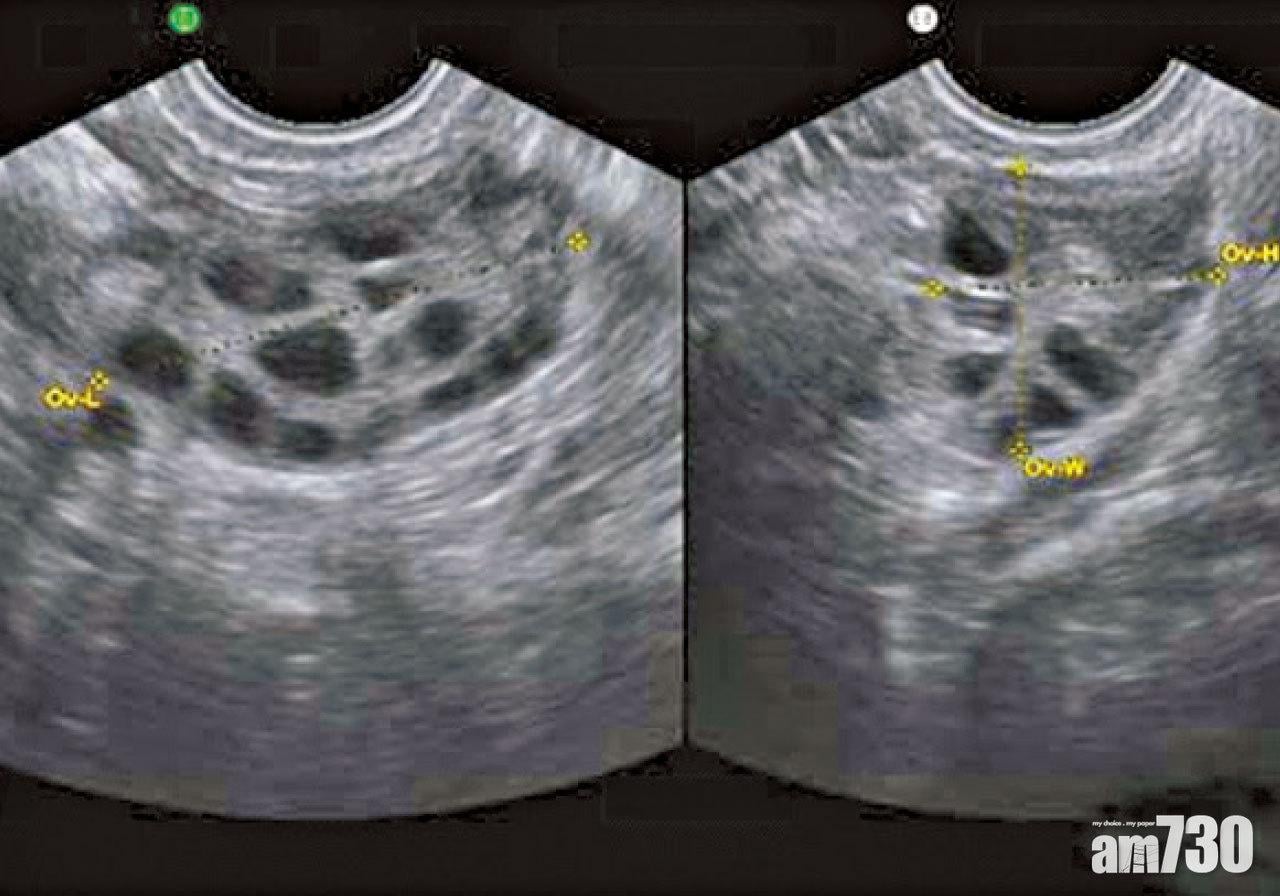

多囊卵巢綜合症是以雄激素過多、持續無排卵和B型超聲波檢查見到卵巢多囊改變為特徵的婦科內分泌疾病。主要會有月經量少、月經稀發、閉經等月經不調的表現,還有肥胖、多毛、痤瘡等外貌改變,以20至35歲的育齡期婦女最多見。在中醫的角度,多囊卵巢綜合症屬於「月經後期」、「閉經」、「崩漏」、「不孕」等範疇之內。多囊卵巢綜合症主要以脾腎兩虛為本,兼夾氣滯、血瘀、痰濕等阻滯於胞宮之中,致沖任不通,而令經水難行。